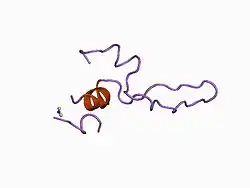

The extracellular N-terminal domain of this protein adopts a tertiary structure consisting of a few helical turns and a disulfide-cross linked loop. It is required for interaction of the cholecystokinin A receptor with its corresponding hormonal ligand.[6]

- ^ Pellegrini M, Mierke DF (Nov 1999). "Molecular complex of cholecystokinin-8 and N-terminus of the cholecystokinin A receptor by NMR spectroscopy". Biochemistry. 38 (45): 14775–83. doi:10.1021/bi991272l. PMID 10555959.